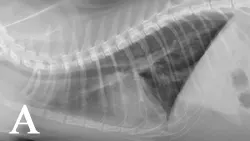

Thoracic radiographs showed lesions suggestive of heartworm or lungworm infection (Figure 1). An in-clinic heartworm antigen test was positive. The owners declined echocardiography.

FIGURE 1

Bronchointerstitial pattern in the caudal lung fields (A and B). Enlargement of the caudal pulmonary arteries is evident on the ventrodorsal (B) projection.

In symptomatic cats, a positive antigen test is considered diagnostic of a mature infection but a negative result is ambiguous. Cats have few adult worms, so the amount of circulating antigen may fall below the detection limit. Male-only infections can also lead to false-negative results. The presence of antibodies indicates exposure to heartworm but does not necessarily denote an adult infection. Conducting both antibody and antigen testing increases sensitivity of detection as compared with conducting either test alone.1 Radiographic lesions (eg, hyperinflation, varying patterns of parenchymal infiltrates, enlarged caudal pulmonary arteries) help support a diagnosis of heartworm but are nonspecific and can resolve within a few months of infection in cats.5,6 Echocardiography provides a definitive diagnosis if heartworms are observed.